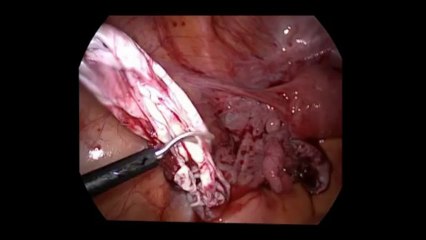

Diagnostik laparoskopi - Prof. Dr. Aydan Biri